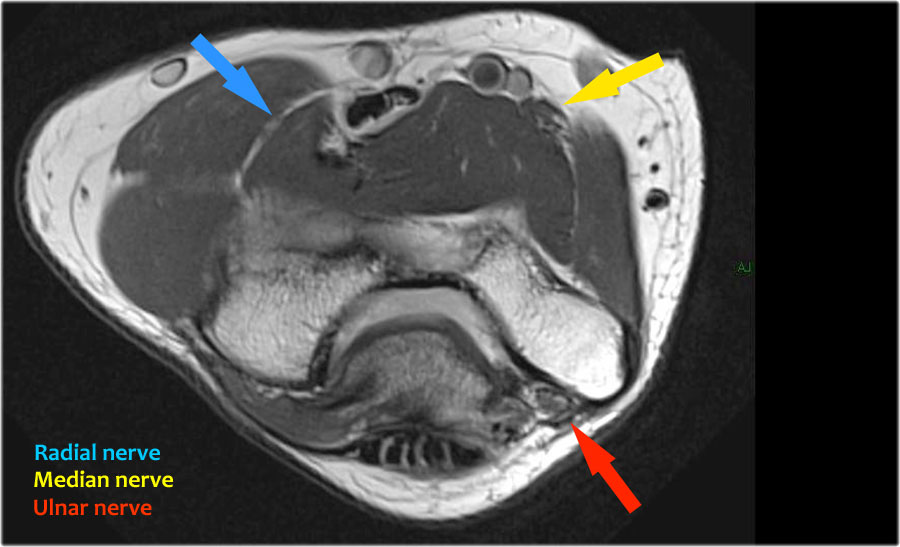

Scroll through the images.

Ulnar nerve

Ở đây chúng ta thấy dây thần kinh trụ nằm trong ống trụ.

Bó sau của dây chằng bên trụ tạo thành sàn của ống, trong khi mạc hãm tạo thành trần của ống.

Radial nerve

Dây thần kinh quay có thể được xác định rõ nhất ở mức chỏm xương quay, nơi có thể quan sát thấy các nhánh nông và nhánh sâu trong ống xương quay (mũi tên).

This is a very consistent place to find the radial nerve.